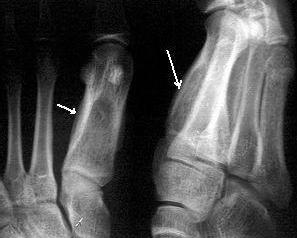

手足短骨骨干结核较为常见。结核由血循环侵犯短骨骨干而致病。病人多为10岁以下儿童,成年人和老年人少见,病变也常多发。